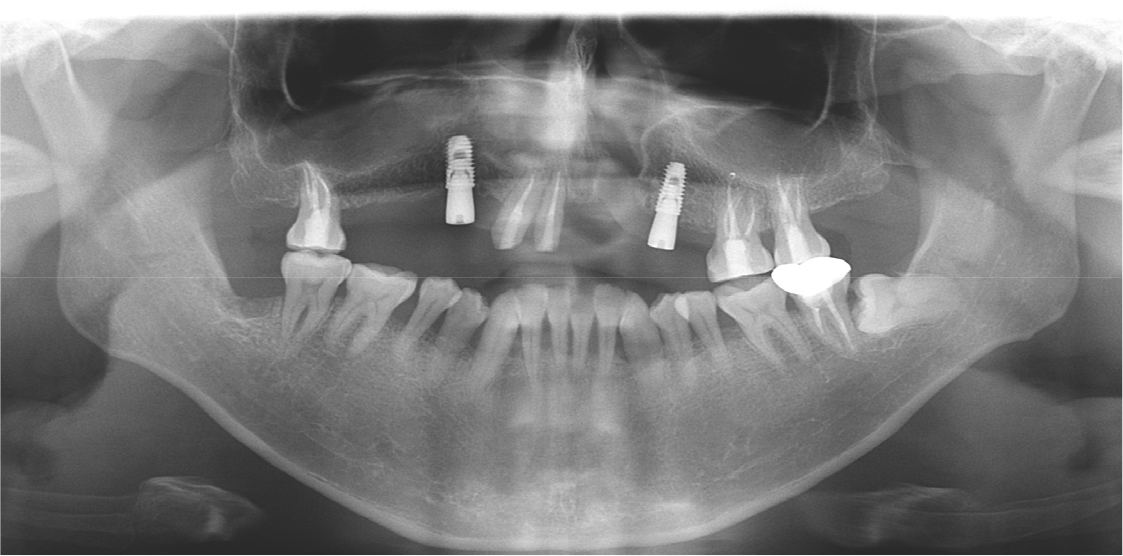

Two implants were placed in the maxillary right and left canine positions to achieve stable stress distribution in the abutments (TSIII, 4.0 × 10.0 mm; Osstem, Seoul, Korea) (Fig. 3). Intentional root canal treatment was performed on the remaining maxillary teeth to create a 4-mm interocclusal space required for the use of a hybrid telescopic double crown. For definitive prosthesis fabrication, a silicone impression was made using polyvinyl siloxane (Aquasil Ultra XLV and Aquasil Ultra LV; Dentsply Sinora, Philadelphia, PA, USA) for the maxillary implants and teeth using an individualized tray (Fig. 4). The inner crown, outer crown, and metal framework of the final prosthesis were made of Co–Cr alloy (VeraBond 2V; Aalbadent, Fairfield, CT, USA) (Fig. 5).14 For each abutment and implant, the spark erosion method was used to form a channel of approximate diameter under 0.8 mm for placing the friction pin in the mesial or distal region. A friction pin was installed in this channel to obtain a retention force. The axial convergence angle of the inner crown was set at 2 degrees, and a chamfer margin was designed to prevent movement between the inner and outer crowns. Laser welding was used to join the outer crowns to the metal framework, and artificial teeth were arranged using the group function concept on the metal framework for the wax trial dentures (Fig. 6). The vertical height and centric position of the trial denture were reconfirmed with the patient’s consent after the try-in process in the oral cavity, and a definitive prosthesis was fabricated. Glass ionomer cement was used to fix the inner crown (Fuji I; GC, Tokyo, Japan).